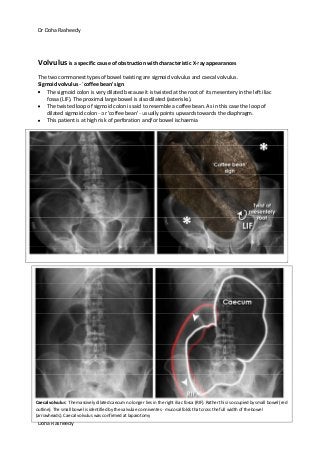

Volvulus is a specific cause of obstruction with characteristic X-ray appearances

The two commonest types of bowel twisting are sigmoid volvulus and caecal volvulus.

Sigmoid volvulus - 'coffee bean' sign

The sigmoid colon is very dilated because it is twisted at the root of its mesentery in the left iliac

fossa (LIF). The proximal large bowel is also dilated (asterisks).

The twisted loop of sigmoid colon is said to resemble a coffee bean. As in this case the loop of

dilated sigmoid colon - or 'coffee bean' - usually points upwards towards the diaphragm.

This patient is at high risk of perforation and/or bowel ischaemia

Caecal volvulus: The massively dilated caecum no longer lies in the right iliac fossa (RIF). Rather this is occupied by small bowel (red

outline). The small bowel is identified by the valvulae conniventes - mucosal folds that cross the full width of the bowel

(arrowheads). Caecal volvulus was confirmed at laparotomy